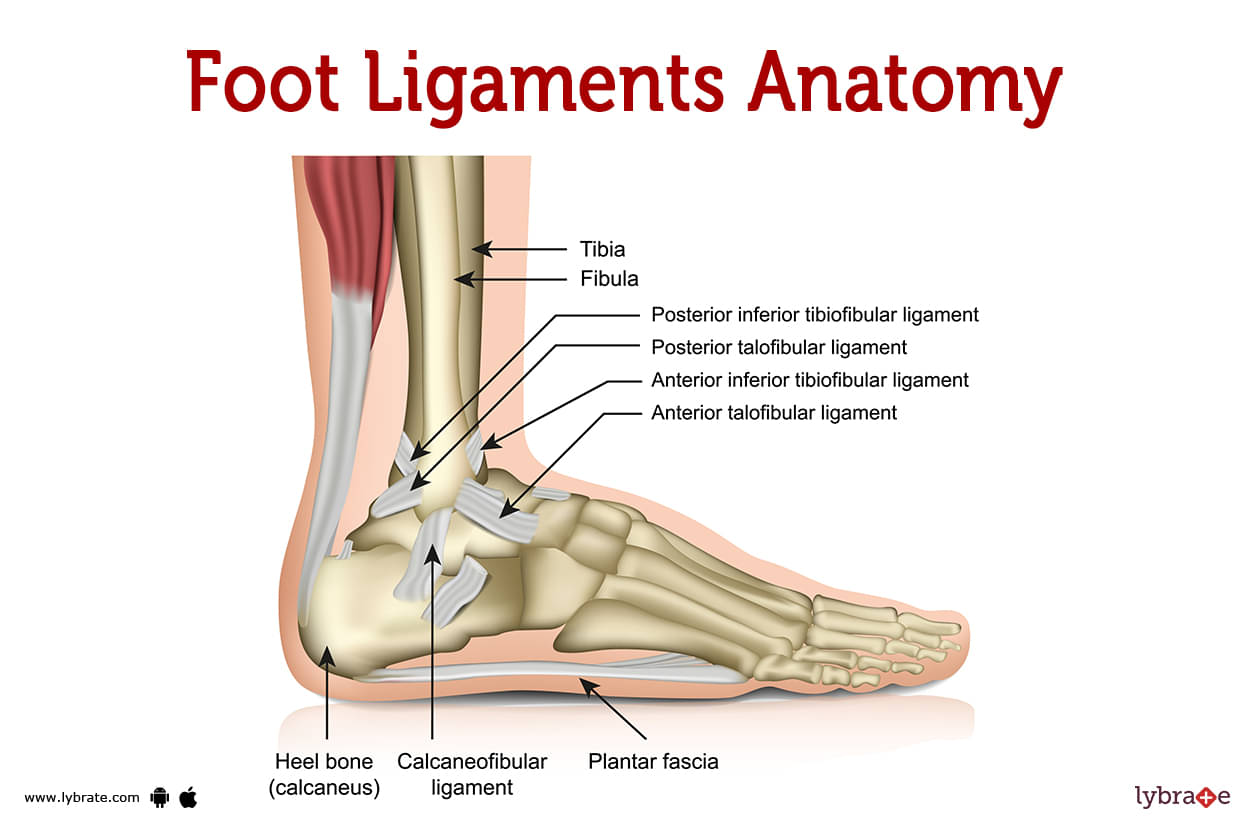

- Lec 3 - Ligaments Diagram | Quizlet

- Ligaments Diagram | Quizlet

- Diagram Of Ligaments | Quizlet